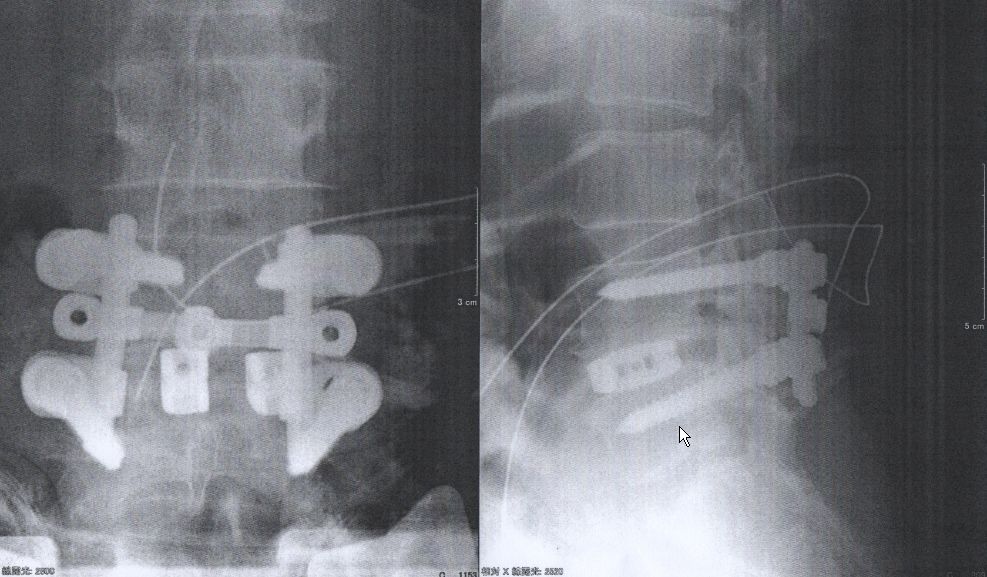

術後のレントゲン写真です(自分もちろん意識ないです)

はい、第4-5背骨の間にチタンのかごが入って

後方からボルトと金具で留まっているのが分かります。